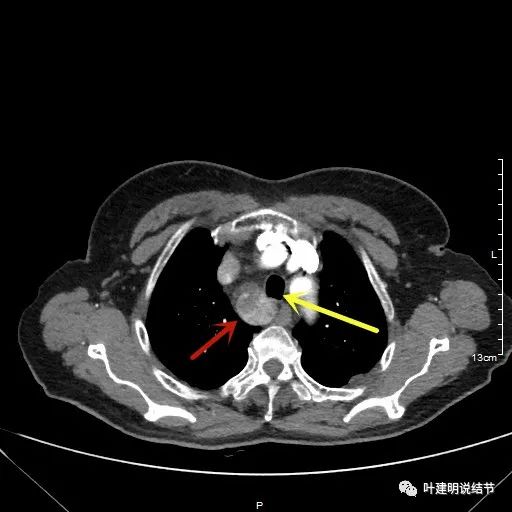

胸顶就开始有肿瘤了,黄色示受压迫移位的气管,红色示肿瘤